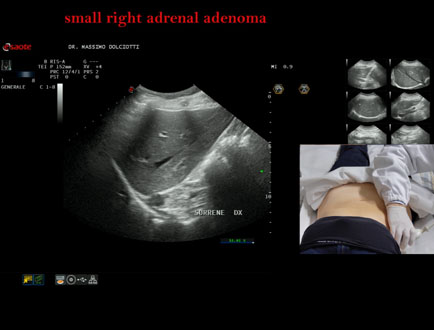

Data inserimento: 06/11/2025

Ecografia del: 31/10/2025

Strumento: Esaote MyLab Eight

Sonda: Convex Multifrequenza 1-8 MHz

Età Paziente: F 69 anni

Motivazione dell'esame: follow up per piccolo adenoma surrenalico.

Commento all'esame: le immagini ed il video documentano in sede surrenalica destra, formazione ipoecogena, a margini definiti, rotondeggiante, delle dimensioni di 15,8 x 14,8 mm, da ricondurre ad adenoma surrenalico.

Conclusioni: piccolo adenoma surrenalico destro (small right adrenal adenoma).

Presentazione: Dr. Massimo Dolciotti - Ancona